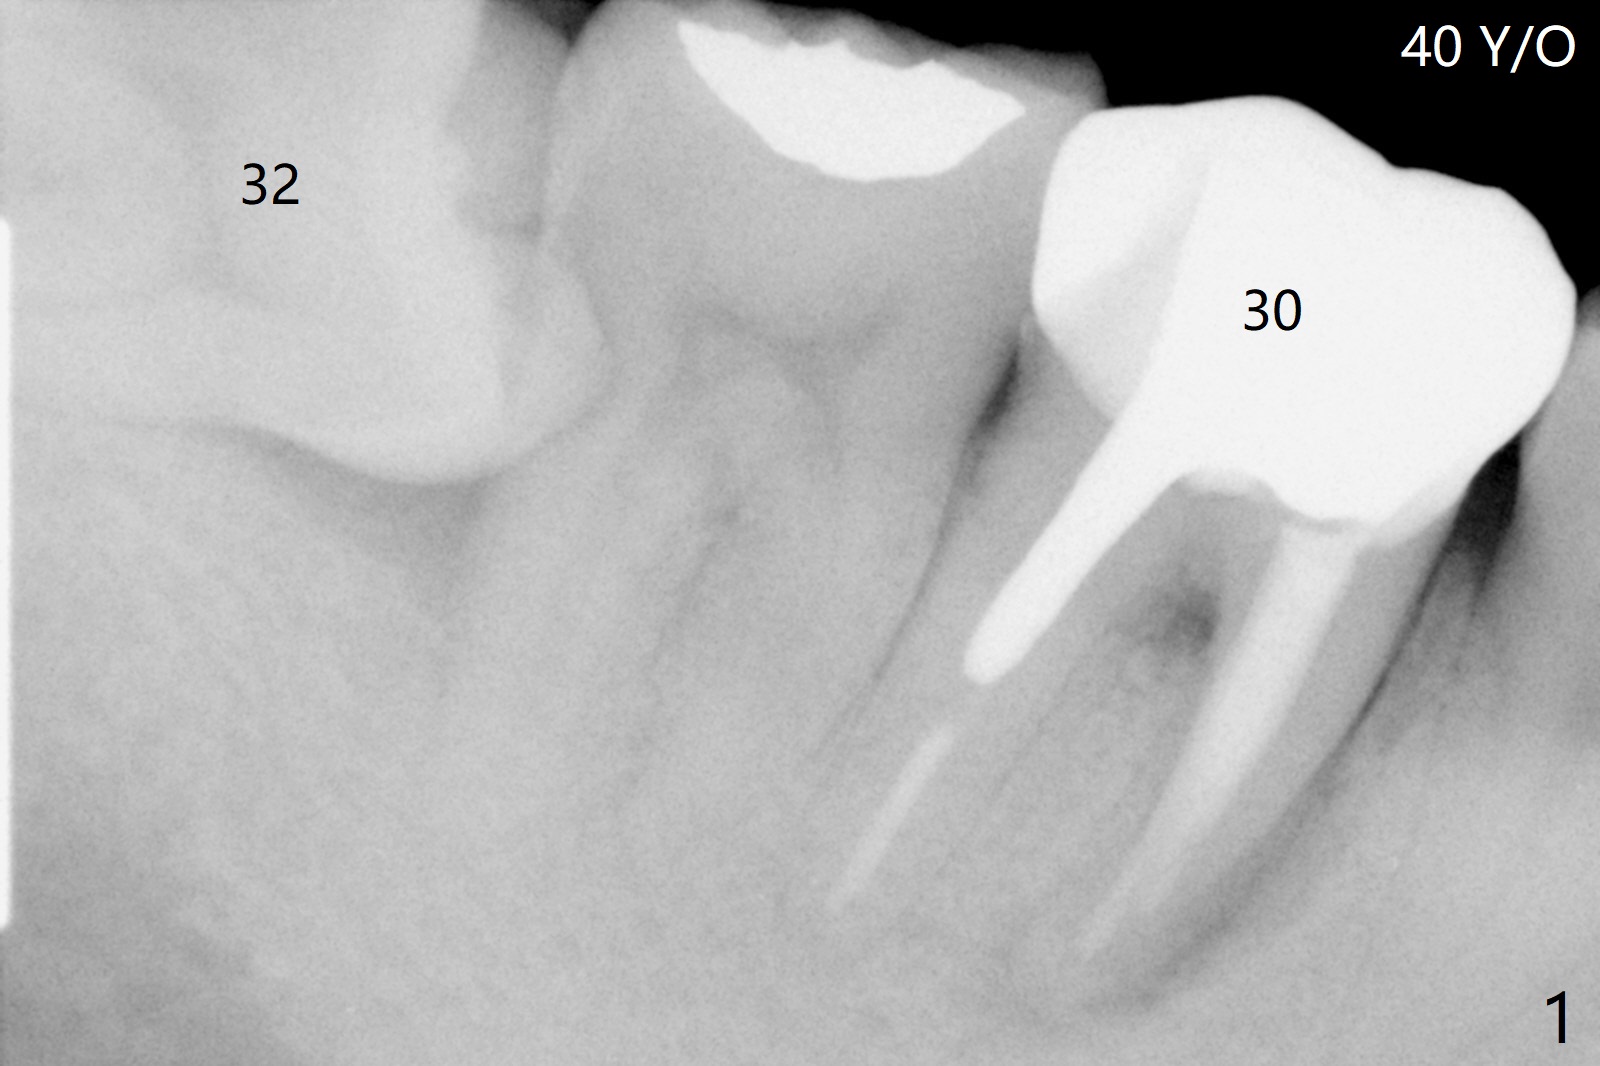

No Bone Graft: Defect heals By Itself

A 40-year-old man had the tooth #32 extracted without bone graft immediate post #30 implant placement (Fig.1,2). The distal bony defect of the tooth #31 appears to have been repaired 4 years postop (Fig.3,4).